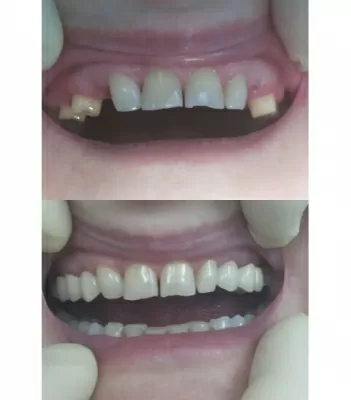

С лета 2018 лечусь в клинике Лигадент у доктора Трошян Тиграна Гамлетовича. За это время доктор восстановил мне все зубы, при лечении которых ранее были допущены, мягко говоря, ошибки. Произвел впечатление очень ответственного, грамотного, образованного специалиста с большим опытом, Это настоящее счастье, когда с тобой работает профессионал такого уровня! Далее мне поставили читать далее